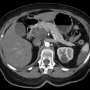

The pancreas, a vital gland located behind the lower part of the stomach, plays a key role in regulating blood sugar and assisting with food digestion. When cancer develops in this organ, it can severely impact overall health and often leads to dire consequences if not caught early.